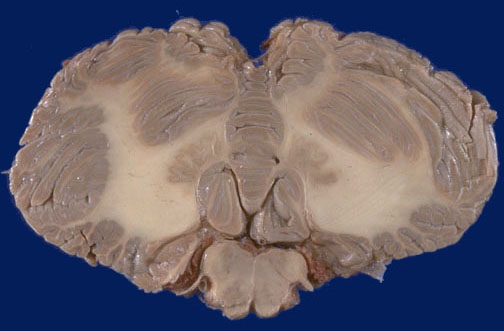

Identify the following regions of the normal brain in the image above: Dentate nucleus - IX cranial nerve - Pyramid of medulla oblongata - Cerebellar vermis